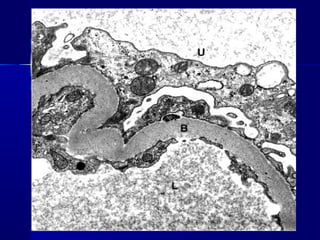

 MICORANGIOPATÍA DIABÉTICAMICORANGIOPATÍA DIABÉTICA : engrosamiento: engrosamiento

difuso de las membranas basales de las arterias peque-difuso de las membranas basales de las arterias peque-

ñas y de los capilares (evidente en piel, retina, músculoñas y de los capilares (evidente en piel, retina, músculo

esquelético). También afecta a túbulos renales, cápsulaesquelético). También afecta a túbulos renales, cápsula

de Bowman, nervios periféricos.de Bowman, nervios periféricos.

 MICORANGIOPATÍA DIABÉTICAMICORANGIOPATÍADIABÉTICA : engrosamiento: engrosamiento difuso de las membranas basales de las arterias peque-difuso de las membranas basales de las arterias peque- ñas y de los capilares (evidente en piel, retina, músculoñas y de los capilares (evidente en piel, retina, músculo esquelético). También afecta a túbulos renales, cápsulaesquelético). También afecta a túbulos renales, cápsula de Bowman, nervios periféricos.de Bowman, nervios periféricos.  NEFROPATÍA DIABÉTICA:NEFROPATÍA DIABÉTICA: - Afectación glomerular da lugar a proteinuria progresi-- Afectación glomerular da lugar a proteinuria progresi- va con IRC. Glomerolosclerosis nodular (lesiones deva con IRC. Glomerolosclerosis nodular (lesiones de Kimmelstiel-Wilson)Kimmelstiel-Wilson) - Vascular: arteriosclerosis- Vascular: arteriosclerosis - Infección: ITU, con pielonefritis.- Infección: ITU, con pielonefritis.